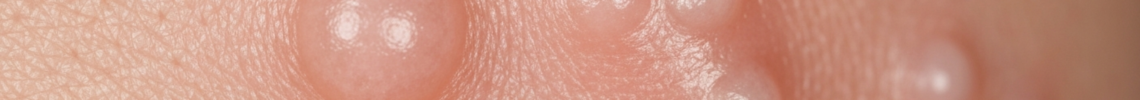

When examining milia symptoms pictures, the most prominent visual characteristic is the appearance of small, raised, dome-shaped bumps on the skin. These lesions are typically white or yellowish, firm to the touch, and non-tender. Unlike acne or other inflammatory lesions, milia do not have a central pore or opening, nor do they exhibit signs of inflammation such as redness, swelling, or pus. They are essentially tiny cysts filled with trapped keratin, a protein found in skin, hair, and nails.

The size of individual milia usually ranges from 1 to 2 millimeters in diameter, though they can sometimes be smaller or slightly larger. They often appear in clusters, especially around the eyes, nose, and cheeks, but can also be found on other parts of the face and body. The distinct coloration—often described as pearly white or creamy yellow—is a key identifier in milia appearance. These keratin cysts are superficial, lying just beneath the outermost layer of the skin (epidermis), which contributes to their characteristic opaque look.